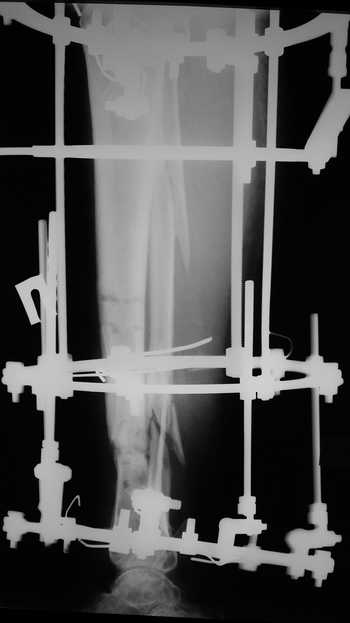

Женщина 46 лет, неудачно лечившаяся по поводу перелома голени в нижней 1\3

сначала в гипсе,  поступила через 6 месяцев после остеосинтеза пластиной

(рис 1). Имелась деформация в нижней 1\3 голени: варус, антекурвация,

наружная ротация, два свища. Удалена пластина, дебридмент мягких тканей,

остеотомия м\б кости, аппарат Илизарова. По рентгенограммам в двух проекциях

произведено планирование устранения смещений (рис 2 и 3), между вторым и

третьим кольцом установлены 6 телескопических дистракторов Гесапода, данные

введены в программу, и далее втечение 10 дней больная подкручивала телескопы

согласно выданной компьютером инструкции. По завершению репозиции

гексаподные телескопы обратно заменены на обычные штанги от аппарата

Илизарова (рис 4 и 5). Еще через две недели забит гвоздь (рис 6, контроль

через 4 месяца).